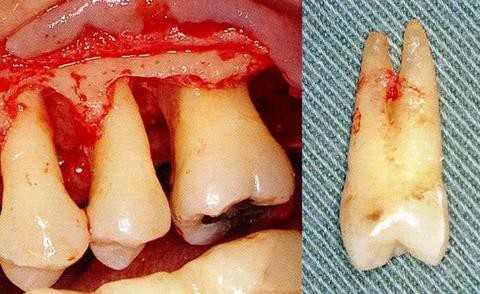

▼圖6-4 下頜第二后磨牙的融合根。在根尖的組合部的產(chǎn)生了附著喪失,導(dǎo)致急速惡化。